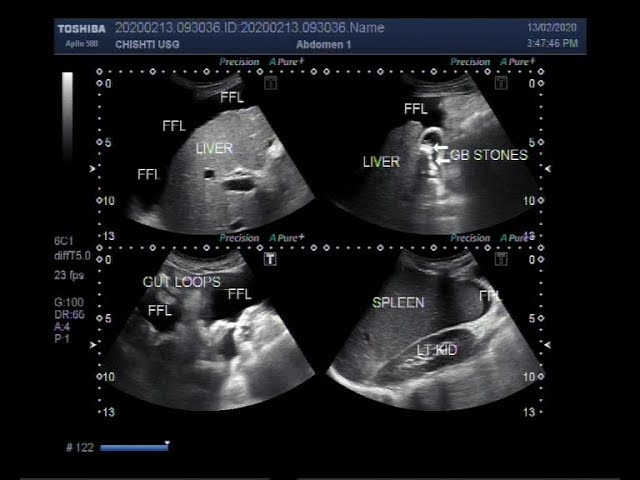

Siêu âm đàn hồi gan là phương pháp siêu âm nhằm đánh giá mức độ xơ hoá gan phổ biến nhất trên thế giới. So với sinh thiết, đây là phương pháp không xâm lấn với độ chính xác cao. Do đó, kỹ thuật này được xem là một sự lựa chọn tối ưu giúp người bệnh đánh giá sức khoẻ gan toàn diện nhất.

Hình ảnh siêu âm gan (Nguồn: Internet)

Siêu âm đàn hồi mô gan là phương pháp siêu âm có độ chính xác cao dùng để đánh giá độ đàn hồi của các mô tại khu vực này (đơn vị kPa). Đồng thời, đây còn là phương pháp không xâm lấn có khả năng khắc phục hạn chế của xét nghiệm sinh thiết trong việc xác định xơ hoá gan hay viêm gan.

Hình ảnh cho thấy gan bị xơ hoá (Nguồn: Internet)

Ý nghĩa của siêu âm đàn hồi mô gan

Xơ hóa gan là đáp ứng của nhu mô gan với quá trình viêm mạn tính. Đánh giá mức độ xơ hóa gan có ý nghĩa quan trọng trong chẩn đoán giai đoạn, đưa ra quyết định điều trị, theo dõi hiệu quả điều trị và tiên lượng. Tiêu chuẩn vàng trong đánh giá độ xơ hóa gan là sinh thiết gan. Tuy nhiên, đây là kỹ thuật xâm nhập, tiềm ẩn biến chứng, ít được người bệnh chấp nhận, khó lặp lại và khó áp dụng cho đông đảo người bệnh.

Vì vậy, siêu âm đàn hồi mô gan là một sự lựa chọn thay thế vô cùng tốt và tiềm năng. Đây là kỹ thuật mới và được sử dụng rộng rãi bởi tính chính xác, khả năng phát hiện xơ gan cao, dễ thực hiện, có thể lặp lại nhiều lần trong quá trình theo dõi bệnh.

Ngoài ra, siêu âm đàn hồi mô gan sử dụng các chỉ số định lượng, tạo tính khách quan, không phụ thuộc người làm và người bệnh nhưng lại mang đến kết quả chính xác. Trong số các kỹ thuật siêu âm đàn hồi mô hiện nay, kỹ thuật Shear Wave Elastography (SWE) có nhiều ưu điểm vượt trội, mang lại giá trị chẩn đoán cao trong xơ hóa gan. Hiện kỹ thuật này đang được đội ngũ bác sĩ chuyên môn của Bệnh viện Quốc tế Hoàn Mỹ Đồng Nai áp dụng.

Kết quả siêu âm đàn hồi mô gan:

Độ cứng của gan (kPa) ở các mức độ xơ gan có thể thay đổi phụ thuộc vào nguyên nhân của các bệnh gan mạn tính. Do đó, tùy thuộc vào từng bệnh lý sẽ có độ xơ hóa khác nhau. Theo phân loại Metavir, sự xơ hóa gan được chia thành 5 mức độ như sau:

- F0: không xơ hóa.

- F1: xơ hóa nhẹ, bắt đầu có tổn thương gan, tổn thương với vài xơ hóa khoảng cửa quanh các mạch máu rải rác, không nối với nhau.

- F2: Xơ hóa có ý nghĩa: tổn thương gan trung bình, xơ hóa khoảng cửa quanh các mạch máu và chưa nối với nhau.

- F3: xơ hóa nặng: xơ hóa lan tỏa, các vùng xơ nối với nhau.

- F4: xơ gan giai đoạn cuối, gan không còn chức năng.

Đánh giá xơ hóa gan bằng kỹ thuật siêu âm đàn hồi mô gan là phương pháp chẩn đoán không xâm lấn, có độ chính xác cao tương đương với sinh thiết gan, được thực hiện nhanh chóng, không gây đau đớn hay bất kỳ khó chịu nào cho người bệnh. Bên cạnh đó, kỹ thuật này có chi phí khá hợp lý. Đồng thời, đây còn là bước ngoặt của ngành siêu âm, khắc phục được những tồn tại của sinh thiết gan và đang dần được sử dụng rộng rãi, giúp cho người bệnh có cơ hội tầm soát xơ hóa gan sớm hơn.

Hiện nay, Bệnh viện Quốc tế Hoàn Mỹ Đồng Nai có hệ thống máy siêu âm hiện đại (máy LOGIG S8 Xdclear của hãng GE Healthcare – USA), cùng với kỹ thuật siêu âm SWE đạt tiêu chuẩn quốc tế. Toàn bộ quy trình siêu âm đàn hồi gan đều được thực hiện bởi đội ngũ bác sĩ có kinh nghiệm và được đào tạo bài bản sẽ giúp khách hàng chẩn đoán và điều trị xơ hóa gan trong các bệnh lý gan mạn tính, đặc biệt là viêm gan virus B, C, viêm gan do rượu, gan nhiễm mỡ.